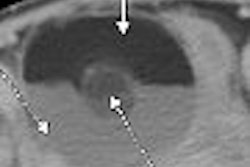

From this it should be evident that, like full-field digital mammography (FFDM), DBT, relying purely on morphologic data, cannot solve the diagnostic problems of breast cancer. Despite its decreased spatial resolution, DBT will almost certainly show most breast lesions more clearly (except for microcalcifications) and increase sensitivity somewhat, but it will do so at the expense of specificity. As a result, the already disgracefully high percentage of negative biopsies performed in the U.S. will continue to rise (Journal of Medical Screening, 2005, Vol. 12:1, pp. 50-54).